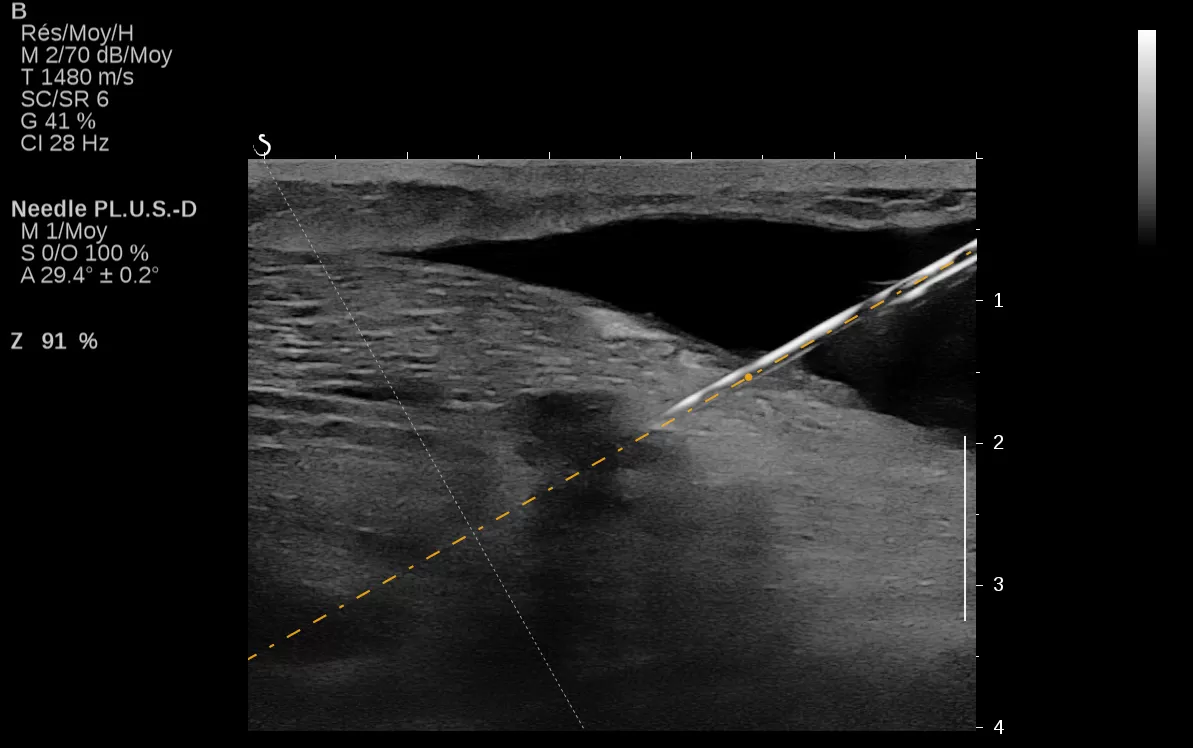

Δείτε πώς με την SWE μπορείτε να αυξήσετε την ευαισθησία και ειδικότητα του υπερηχογραφήματος, την προγνωστική αξία της Βιοψίας αλλά και το πως μπορεί να αναβαθμιστεί ένα DCIS σε IDC.